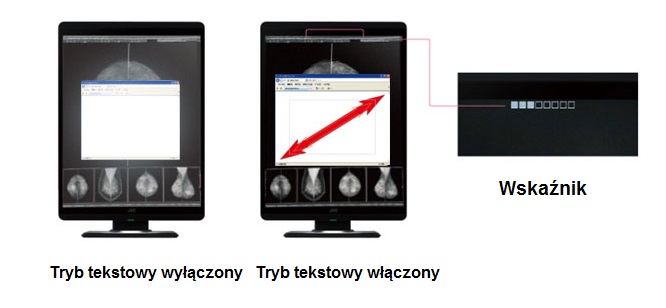

Tryb Tekstowy - Automatyczne zmniejszanie jasności podświetlenia w obszarach tekstowych (ang.: Auto Text Mode).

Automatyczna kontrola jasności obszarów tekstowych, mająca na celu zmniejszenie zmęczenia oczu przy pracy z worklistą lub pisaniu tekstów.